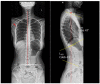

Upper cross syndrome (UCS) is a condition caused from prolonged poor posture manifesting as thoracic hyperkyphosis with forward head and shoulder postures. It has been associated with several other secondary conditions, causing pain and discomfort to those with the condition. This is a case report of a 35-year-old female presenting to clinic with a sharp pain in the neck, upper back, and sternum area for 4 weeks and gastroesophageal reflux disease (GERD). She had been working at home for several months after the shelter at home order was issued. Following evaluation and corrective treatment with cervical adjustment and soft tissue massage, the patient's posture improved and reported full pain resolution. Her symptoms of GERD concurrently resolved as well. She continued to receive chiropractic adjustment two times per month for correcting spinal misalignment. Full restoration of posture was attained on the full spine radiographs at 9 months follow-up. The patient remained symptom-free at 12 months follow-up. Manipulative and preventive therapies aimed at treating and preventing UCS should be more widely adopted to prevent secondary conditions.